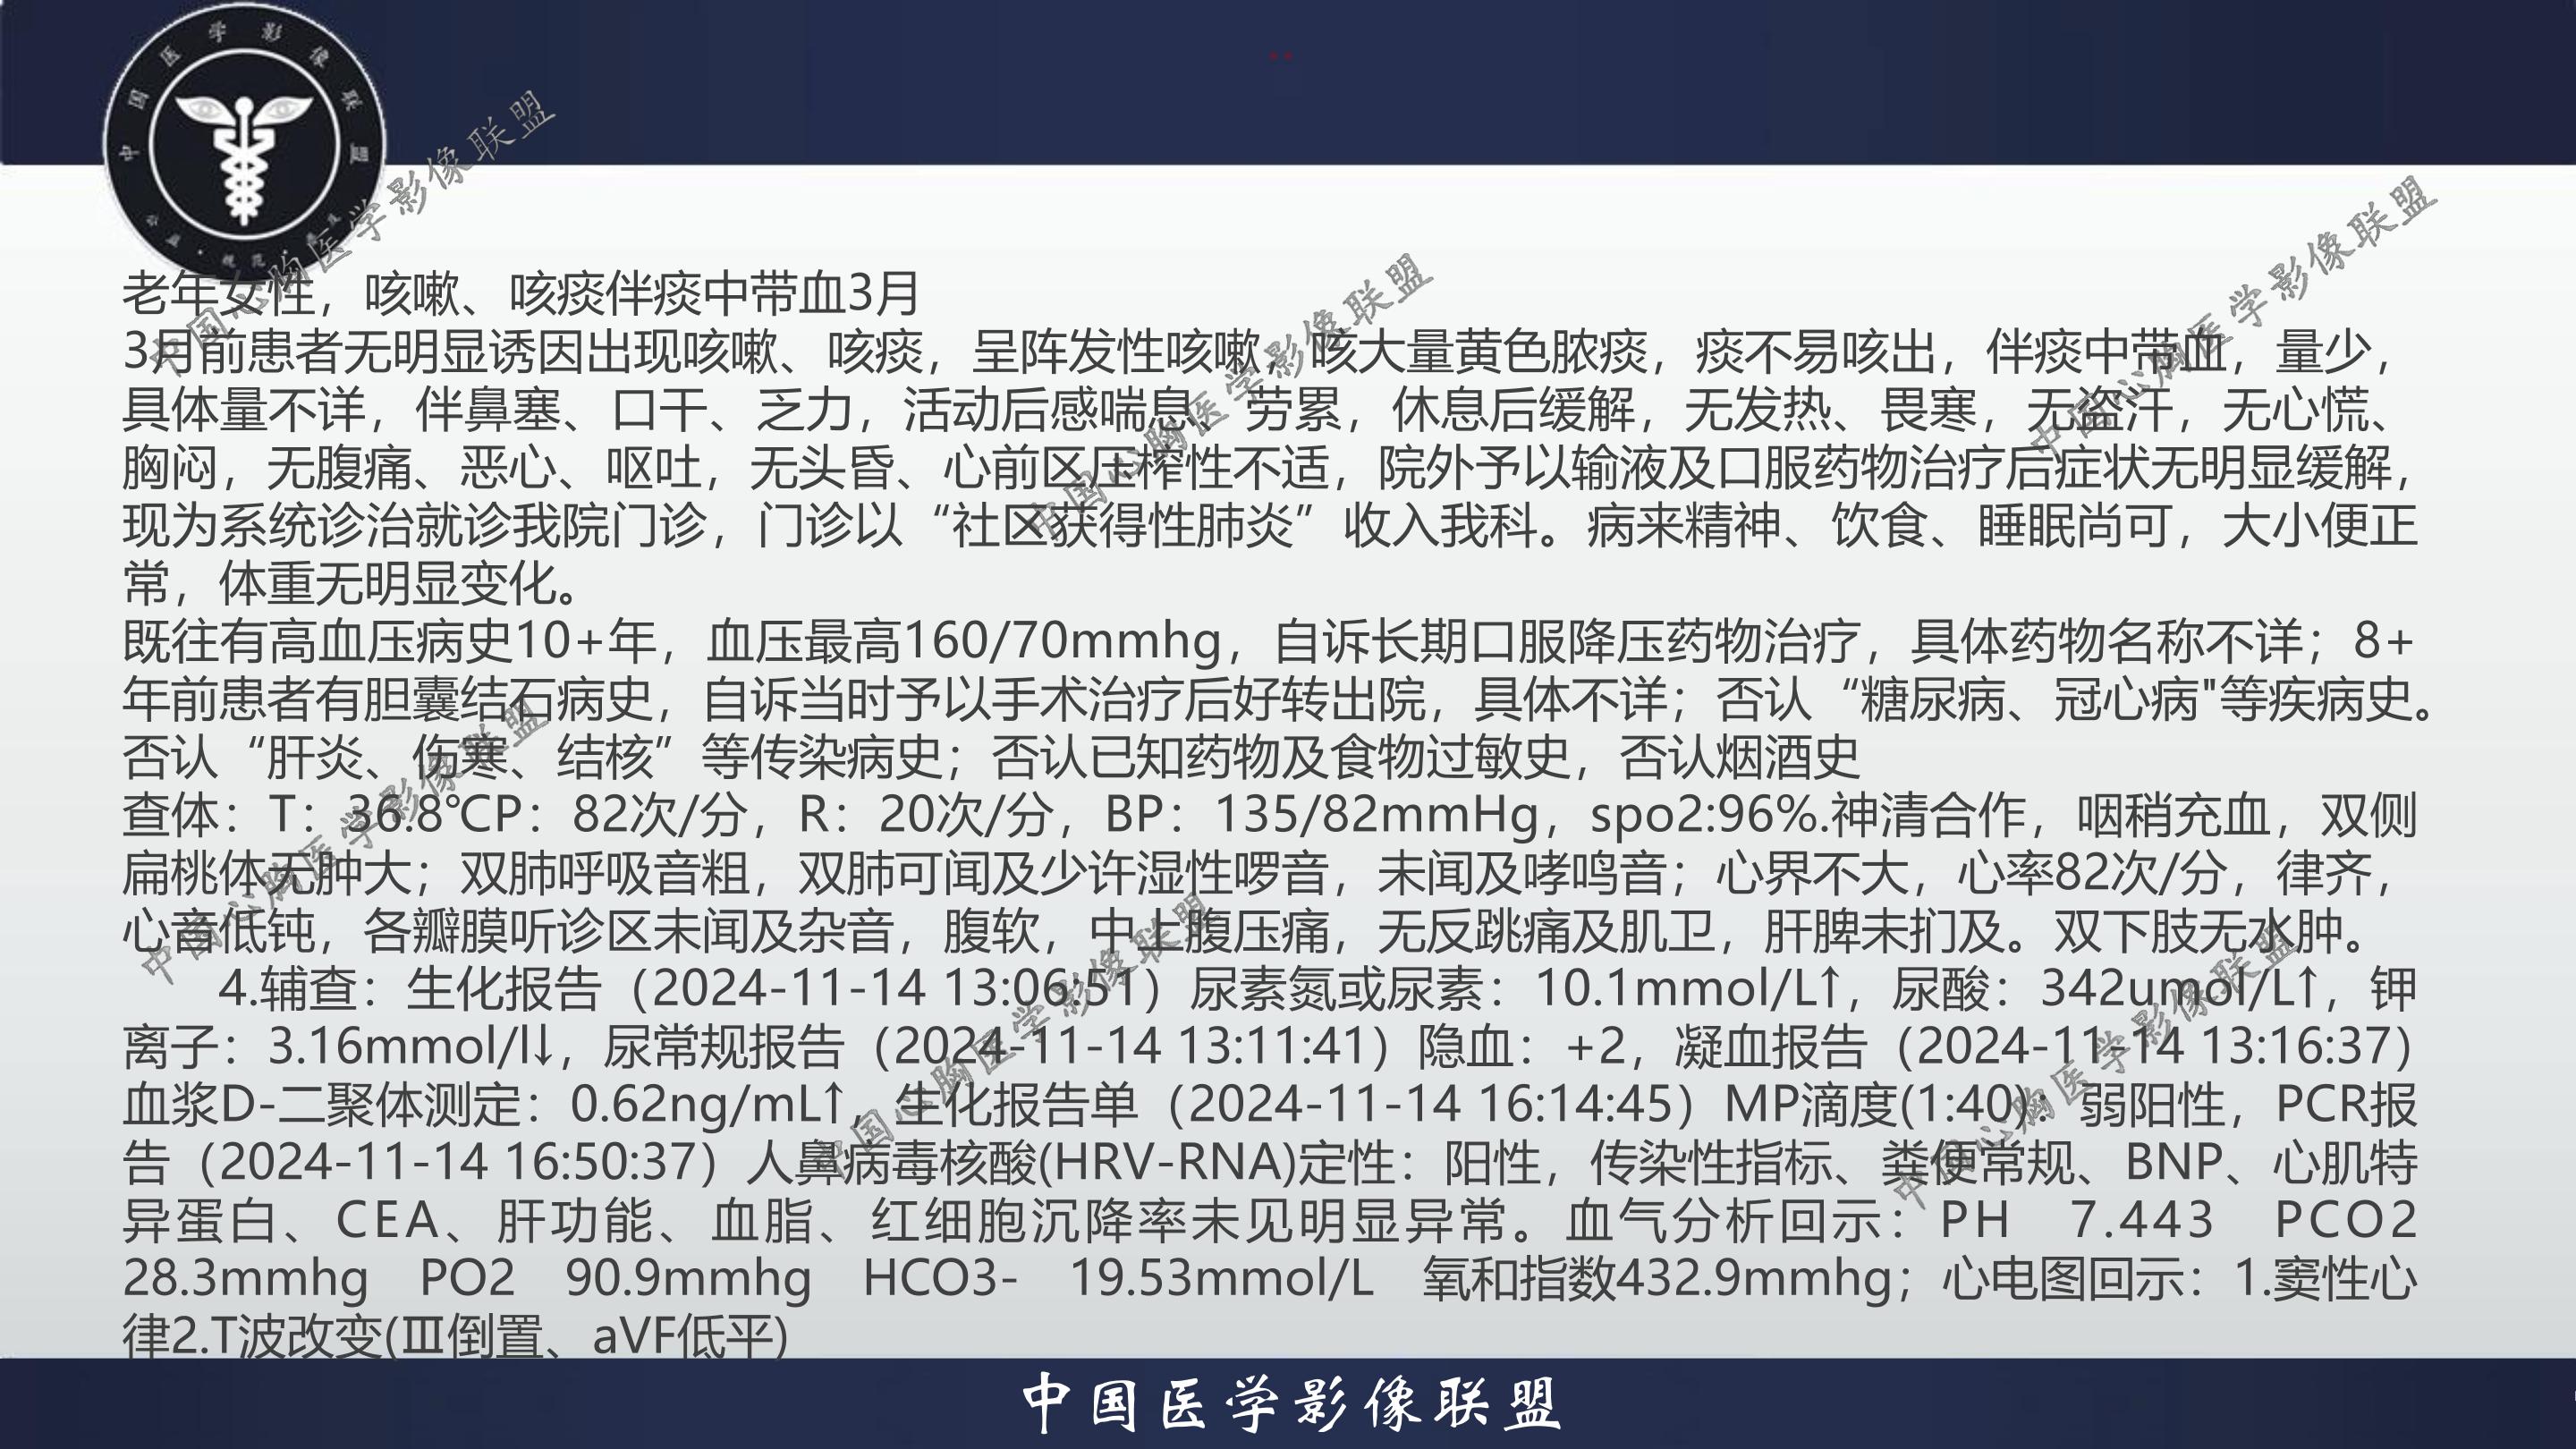

老年女性,咳嗽、咳痰伴痰中带血3月

3月前患者无明显诱因出现咳嗽、咳痰,呈阵发性咳嗽,咳大量黄色脓痰,痰不易咳出,伴痰中带血,量少,具体量不详,伴鼻塞、口干、乏力,活动后感喘息、劳累,休息后缓解,无发热、畏寒,无盗汗,无心慌、胸闷,无腹痛、恶心、呕吐,无头昏、心前区压榨性不适,院外予以输液及口服药物治疗后症状无明显缓解,现为系统诊治就诊我院门诊,门诊以“社区获得性肺炎”收入我科。病来精神、饮食、睡眠尚可,大小便正常,体重无明显变化。

既往有高血压病史10+年,血压最高160/70mmhg,自诉长期口服降压药物治疗,具体药物名称不详;8+年前患者有胆囊结石病史,自诉当时予以手术治疗后好转出院,具体不详;否认“糖尿病、冠心病"等疾病史。否认“肝炎、伤寒、结核”等传染病史;否认已知药物及食物过敏史,否认烟酒史

查体:T:36.8℃P:82次/分,R:20次/分,BP:135/82mmHg,spo2:96%.神清合作,咽稍充血,双侧扁桃体无肿大;双肺呼吸音粗,双肺可闻及少许湿性啰音,未闻及哮鸣音;心界不大,心率82次/分,律齐,心音低钝,各瓣膜听诊区未闻及杂音,腹软,中上腹压痛,无反跳痛及肌卫,肝脾未扪及。双下肢无水肿。

4.辅查:生化报告(2024-11-14 13:06:51)尿素氮或尿素:10.1mmol/L↑,尿酸:342umol/L↑,钾离子:3.16mmol/l↓,尿常规报告(2024-11-14 13:11:41)隐血:+2,凝血报告(2024-11-14 13:16:37)血浆D-二聚体测定:0.62ng/mL↑,生化报告单(2024-11-14 16:14:45)MP滴度(1:40):弱阳性,PCR报告(2024-11-14 16:50:37)人鼻病毒核酸(HRV-RNA)定性:阳性,传染性指标、粪便常规、BNP、心肌特异蛋白、CEA、肝功能、血脂、红细胞沉降率未见明显异常。血气分析回示:PH 7.443 PCO2 28.3mmhg PO2 90.9mmhg HCO3- 19.53mmol/L 氧和指数432.9mmhg;心电图回示:1.窦性心律2.T波改变(Ⅲ倒置、aVF低平)